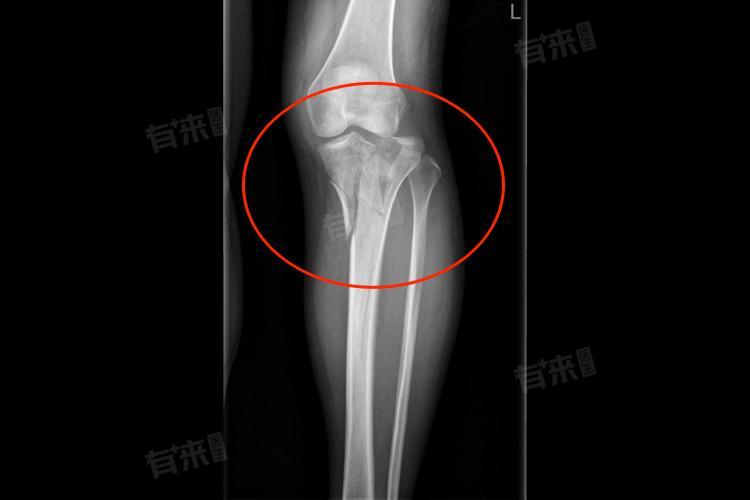

3、右胫骨骨折的诊断:

- 医生通常会进行详细的体格检查,观察受伤部位的肿胀、畸形、压痛情况,检查下肢的感觉、运动和血液循环。

- 影像学检查是确诊的重要手段,X线检查能初步明确骨折的部位、类型和移位情况;对于复杂的骨折,可能需要进一步进行CT扫描,以更精确地评估骨折细节;磁共振成像则有助于判断骨折周围软组织的损伤程度。